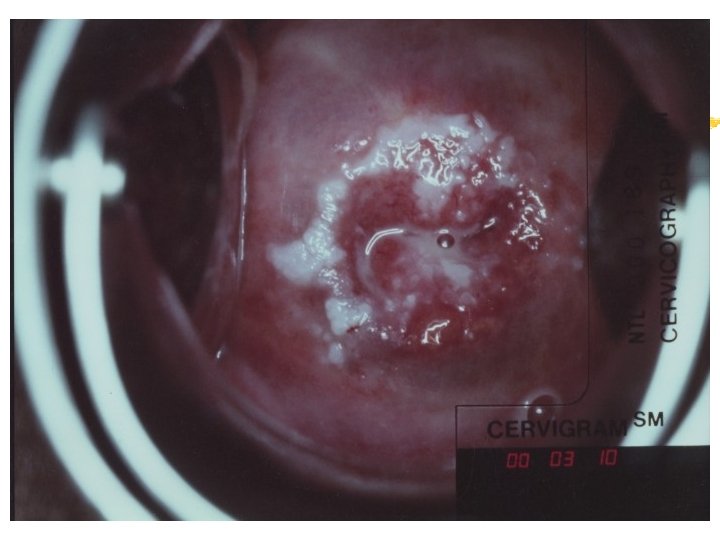

Warning signs of early cervical cancer 1. Yellowish and friable epithelium 2. Abnormal contour 3. Ulceration 4. Atypical vessels 5. Very severe colposcopic atypia 6. Large, significant lesion 7. Canal lesion, going out of range 8. Perimenopausal and post radiation

Atypical transformation zone 1. Acetowhite epithelium 2. Vascular structure a. Mosaic pattern b. Punctation c. Abnormal vessels 3. Leukoplakia

Acetowhiteness 1. SIL …dehydration of nuclear dense lesion 2. HPV …keratin swelling in HPV infected cells 3. Immature squamous metaplasia 4. Healing/regenerating epithelium 5. Congenital transformation zone 6. Inflammation 7. Adednocarcinomas Invasive squamous carcinoma

Vascular structure Mosaic pattern (cobblestone-like appearance). thick whitish areas of small fields polygonal or oval in shape surrounded by reddish borders (fine blood vessels) iodine negative

Vascular structure Punctation … a series of fine red dots on a whitish background. Punctate vessels … dilated, elongated, often slightly twisted and irregular terminal vessels of the hairpin type.

Cervicography: This is NOT Colposcopy High-quality colposcopic-type photography of the cervix Cervicoscope - Hand-held camera with a macrolens and a ring-flash Cervicogram - 35 -mm photo slide is taken Principles Recognition of lesions by means suitable magnification and illumination Fix up the problems of colposcopy 1. a less expensive form 2. noninvasive method 3. do not require expert skill

Procedures of cervicography A) Taking a 35 -mm cervicogram (1) Insert speculum and open as wide as possible … expose an entire cervix and upper vagina (2) Apply first application of 5% acetic acid by dabbing … cleanse the cervix of blood and mucus (3) View the cervix through the cervicoscope … allows time to begin taking epithelial change (4) Apply second application of acetic acid. (5) Take two cervicogram pictures B) Developing the images C) Interpreting a magnified image that was projected on the screen (1) Negative if no definitive lesions are visible (2) Atypical if there was evidence of acetowhite lesion of doubtful significance (3) Positive if there was evidence of a minor or major-grade lesion or cancer